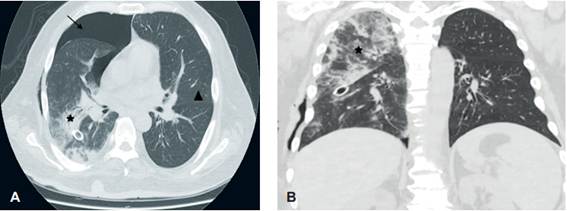

Se realizó PET-CT que reportó neumotórax derecho como hallazgo incidental, confirmado por radiografía de tórax (Figura 1), por lo que se indicó toracostomía cerrada. Durante el procedimiento se evidenció salida de aire a presión y producción de 150 cc de líquido de aspecto seroso; se colocó un tubo de tórax 32 Fr, que se conectó a sistema Pleur-Evac® y succión a -10 cm de agua.

En la radiografía de tórax de control, aproximadamente una hora posterior al procedimiento, se documentaron áreas de consolidación multilobar unilateral derechas y neumotórax residual (Figura 2), por lo que se continuó con succión a -30 cm de agua y se solicitó tomografía computarizada (TC) de tórax, confirmando los hallazgos (Figura 3). Teniendo en cuenta el procedimiento realizado y secuencia de imágenes, se consideró que el paciente cursaba con edema pulmonar por reexpansión. Se inició terapia respiratoria e incentivo respiratorio, y se logró el retiro del tubo de tórax cuatro días después, sin complicaciones. En el seguimiento radiológico al sexto día se apreciaba resolución de los hallazgos imagenológicos (Figura 4).

Aunque la clínica de deterioro respiratorio puede sugerir el diagnóstico, la secuencia de imágenes es la base fundamental. Como primera imagen, la radiografía de tórax posterior al procedimiento usualmente no revela alteraciones parenquimatosas; 2 a 4 horas después se suele evidenciar en más del 90 % de los pacientes un patrón de ocupación alveolar unilateral, que resuelve entre 5 y 7 días, sin secuelas radiológicas. En la TC se demuestran opacidades en vidrio esmerilado, engrosamiento septal, focos de consolidación y áreas de atelectasia usualmente ipsilateral al procedimiento, aunque puede ser bilateral 1.